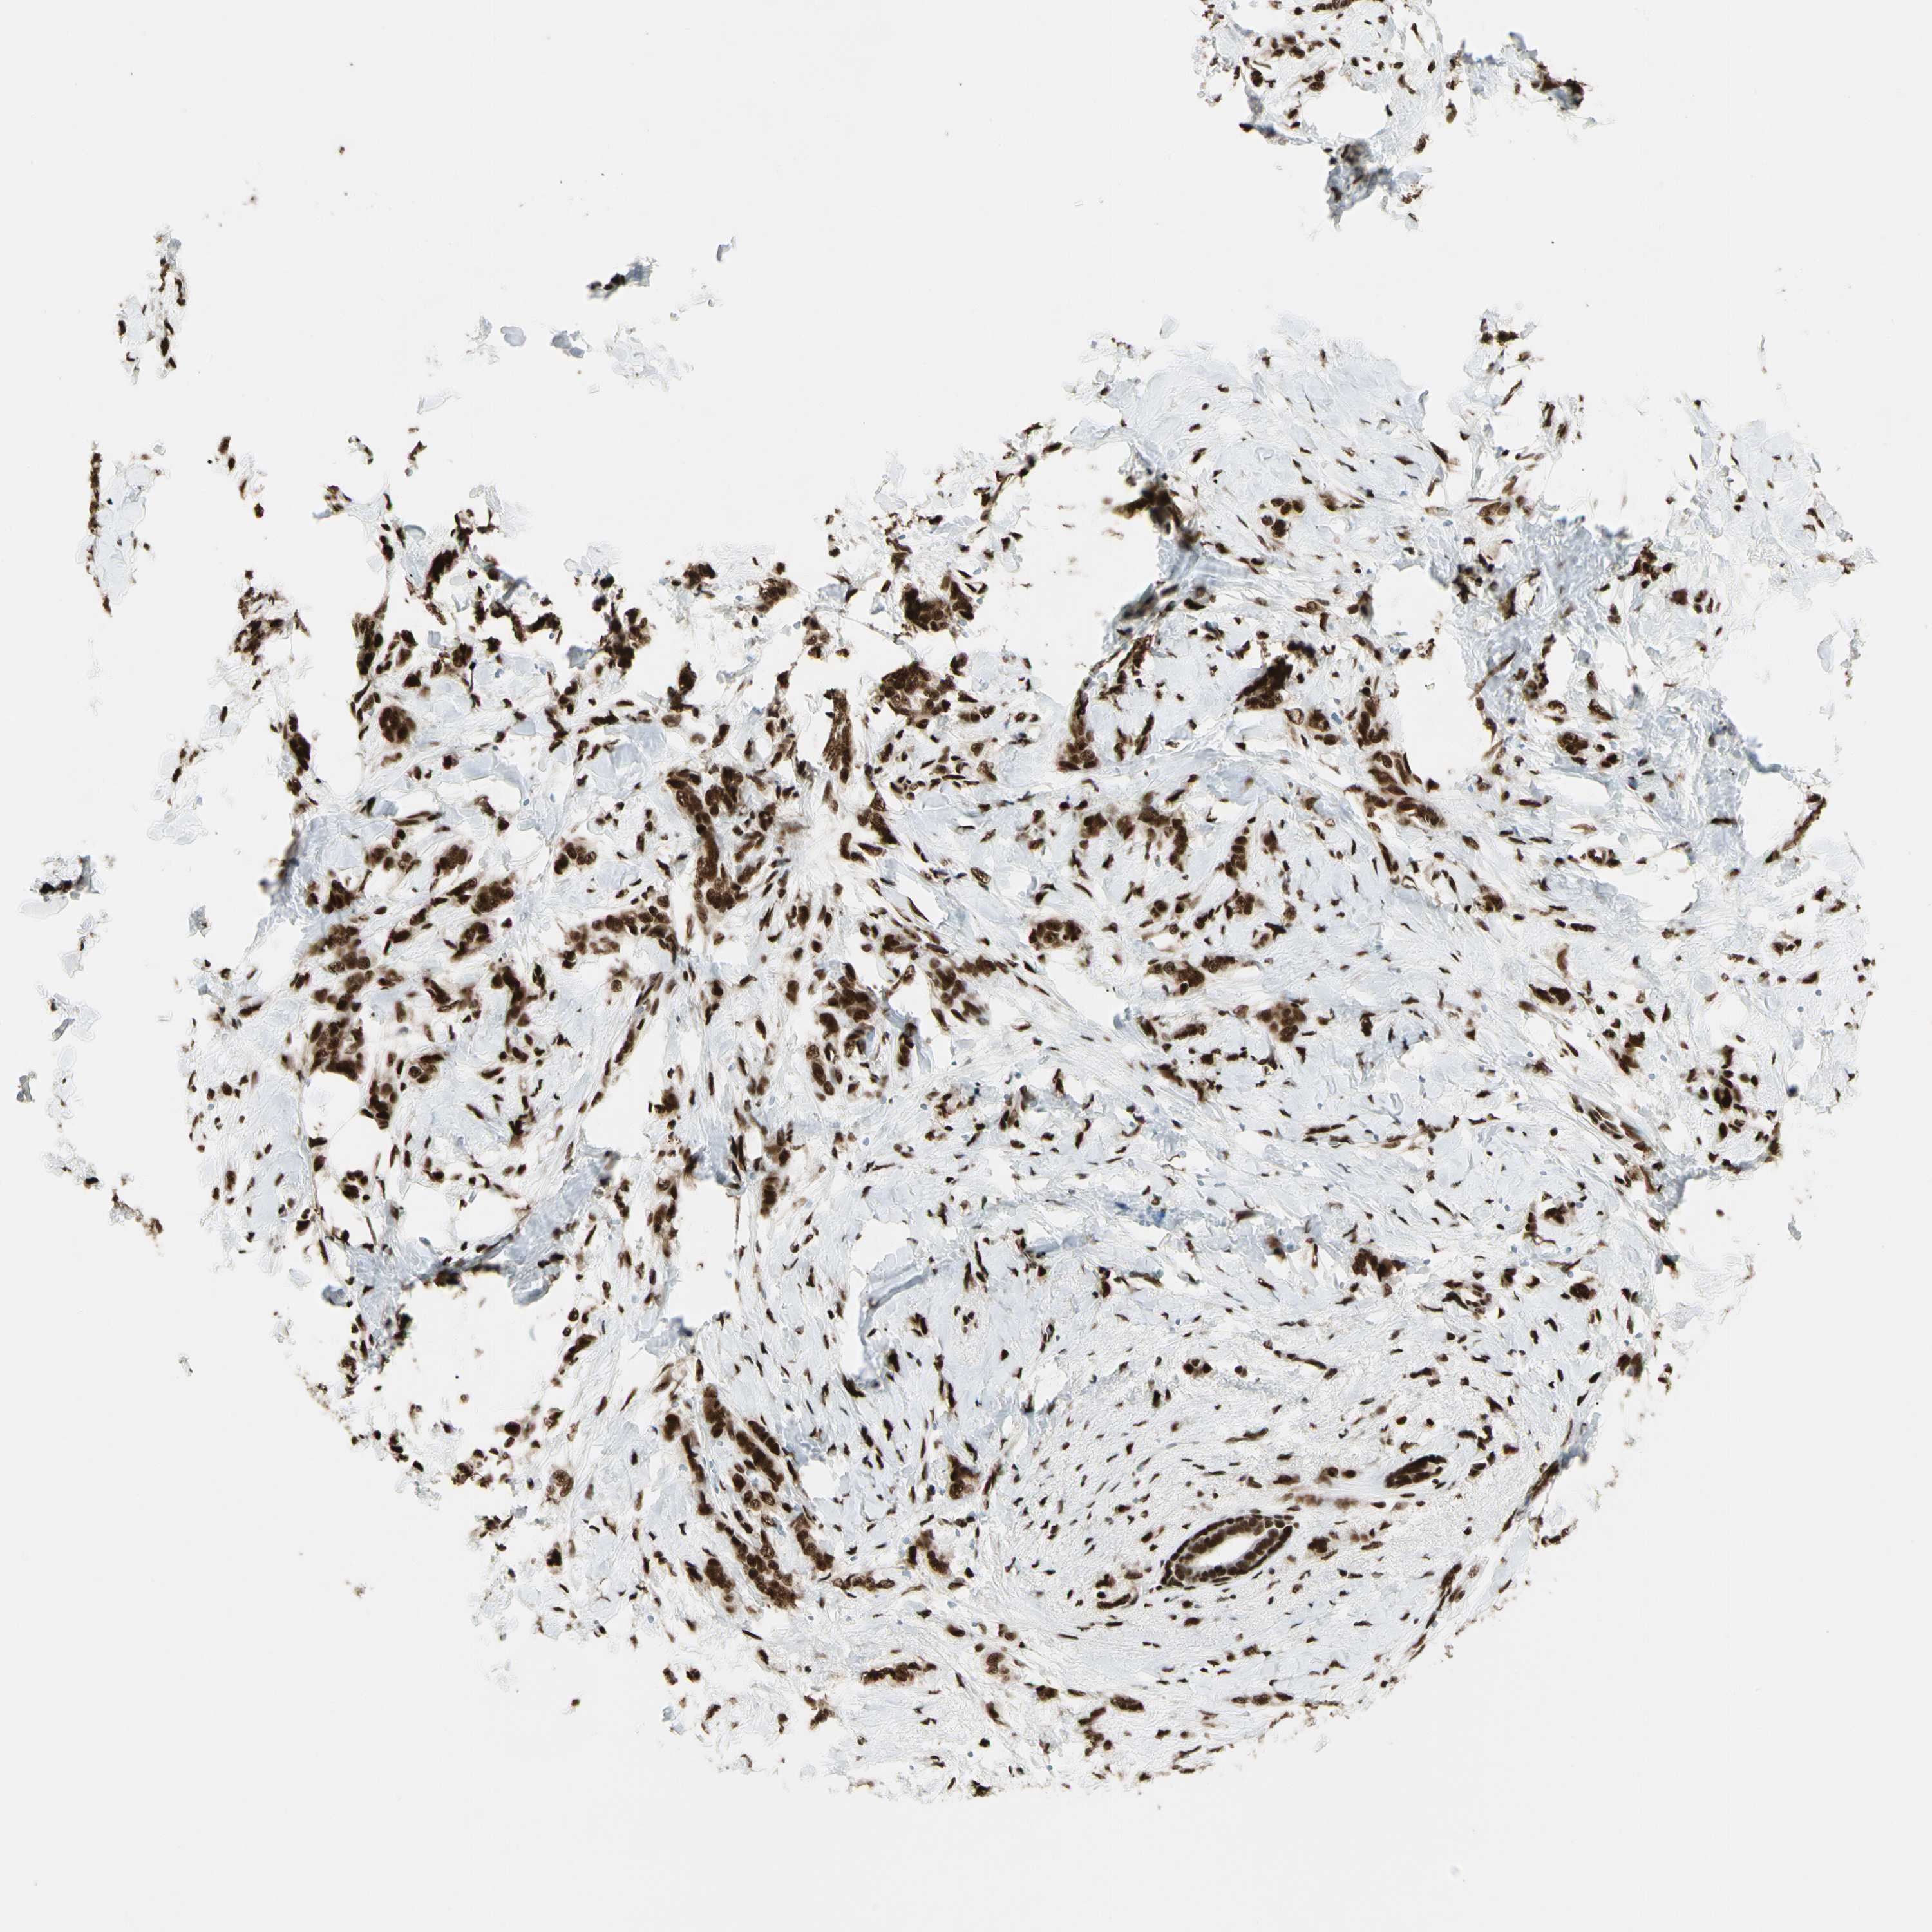

BRCA TCGA BRCA VALIDATION PROTEIN EXPRESSION